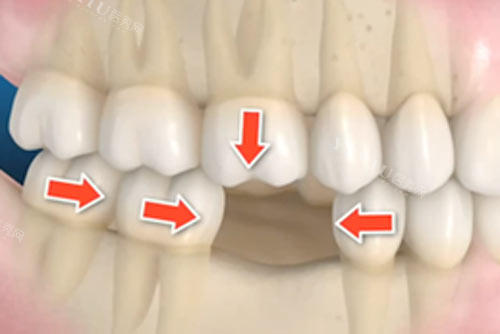

种植牙选择

针对缺牙患者,欣泰口腔提供多种种植方案: